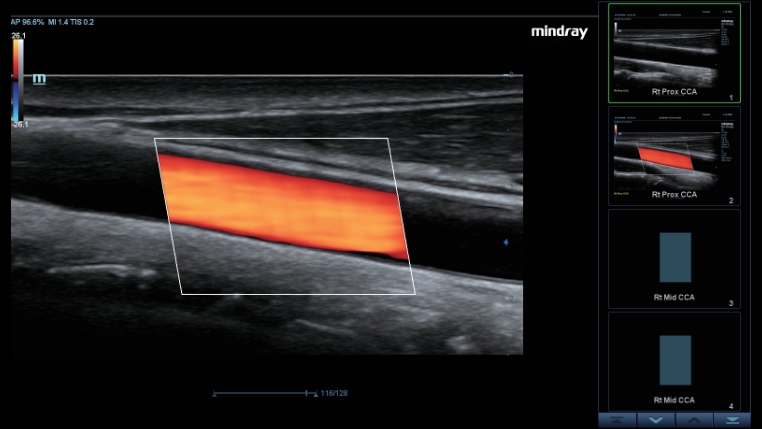

Smart Track

Smart Track? ?? ??? ????? ?? ??? ???? ???? ???? ? ????. ?? ??? ?? ??, ??, PW ????? ????? ??? ?? ???? ??? ???? ? ????. ??? ?? ?? ?????? ??? ?? ??? ?? ??????.